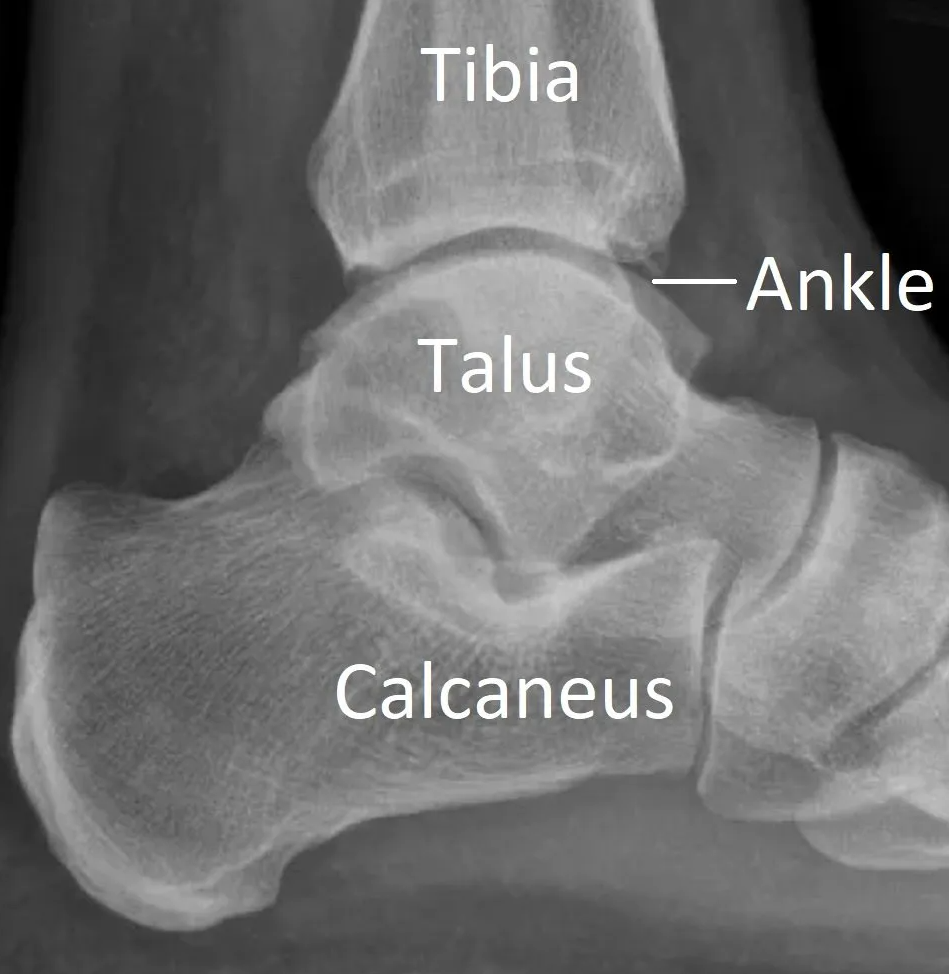

The calcaneus (or heel bone) is the largest bone in the foot. The calcaneus connects to other bones forming the subtalar and calcaneocuboid joints of the hindfoot. The Achilles tendon attaches to the back of the calcaneus.

A fracture is a break in a bone. Calcaneal fractures are uncommon but some are severe injuries. Healing can take many months and long-term complications occur if the joints are damaged or the bone flattened.